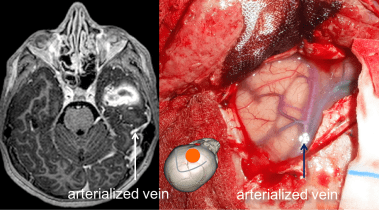

MAV cérébelleuse

les MAV cérébelleuses sont particulièrement dangereuses et sont au premier rang de la mortalité par saignement de MAV.

il s’agit donc d’une indication de chirurgie urgente, sans attendre la dégradation neurologique qui est brutale.

l’imagerie injectée (angioscanner ou comme ici ARM) permet de localiser le nidus par rapport à l’hématome.

opératoirement, devant un cervelet tendu, il est souvent illusoire de tenter de contrôler les pédicules avant d’évacuer l’hématome, cette évacuation est alors le premier temps de l’abord du nidus, qui est ensuite contrôlé en isolant progressivement les afférences artérielles à sa périphérie et en terminant par le drainage veineux.